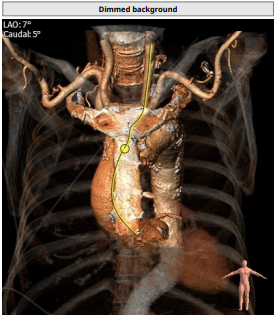

本次的病例解剖上来说是比较大的,所以术者很巧妙的选择了经颈动脉。一方面是因为我们评估患者的腹主动脉瘤,上下的瘤颈不够,不适合行腔内治疗,所以不考虑一站式手术,那么就只能绕行;另一方面,利用颈动脉距离短,控制稳的优势,大胆尝试在大结构的纯反流患者中行TAVR治疗,最后效果完美。

病例难度主要在于患者入路,该患者腹主迂曲且腹主动脉瘤,无法经常规股动脉入路进行植入,广东省医TAVR团队是国内率先开展颈动脉入路的中心之一,李捷教授介绍,经颈动脉入路TAVR的难点在于整个MDT团队的配合,对于手术器械的摆放,术中无菌操作,尤其是释放瓣膜时器械的整体稳定性相比于常规股动脉入路都对整个团队提出更高的要求。此例患者心功能差,且为避免长时间阻断颈动脉对患者远期脑功能造成影响,导管操作时间需尽量控制在20分钟以内,此次此颈入路反流病例,在华南地区,尚属首例。

入路解剖: